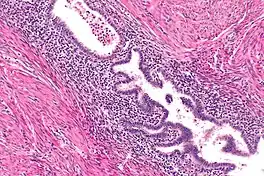

The most common imaging techniques include ultrasound, computed tomography (CT), and MRI. Intravenous pyelography (IVP) has also been used in some cases to assess for possible congenital anomalies of the kidneys.[3] The appearance of these rare tumors on diagnostic imaging has not been extensively described, and in each case documented in the literature, the diagnosis was ultimately made after surgical removal using histologic analysis.[3]

On microscopic examination, patterns of smooth muscle and endometrial tissue must be assessed with care to differentiate adenomyomas from masses of similar appearances, such as endometriosis containing smooth muscle and leiomyomas containing endometriosis.[3]